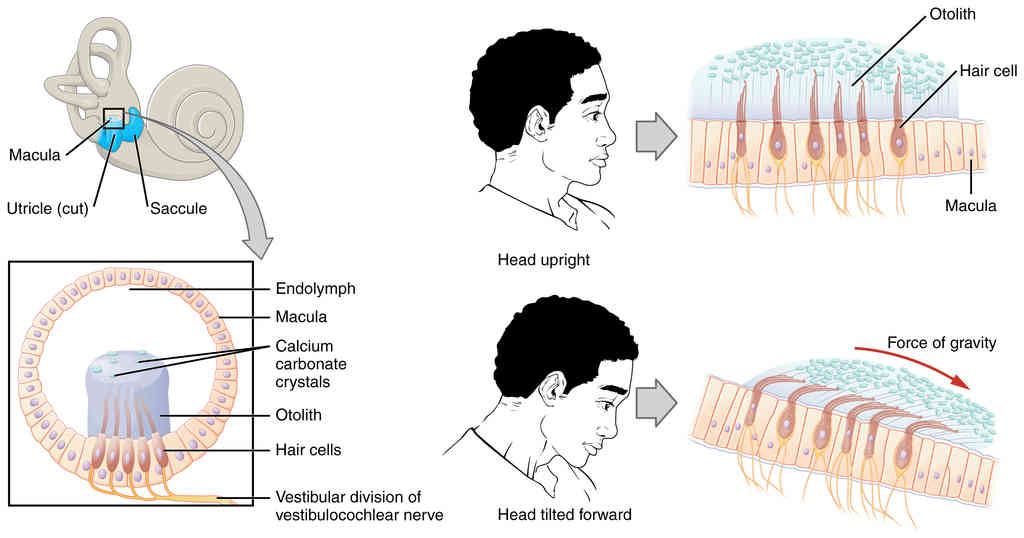

This page is under construction. For now, it is just a resource of the images found in the OpenStax Anatomy and Physiology Handbook. It wil slowly change into a revision tool. Each slide has a number. Use this to refer to the slide. When completed, it will have an unlabelled section, with labelled slides in parallel. On the unlabelled slides, write your answer and use the labelled slide to assess yourself. Keep track by also noting the number on each slide. Improvement at each attempt is important, more so than full marks on a first attempt.